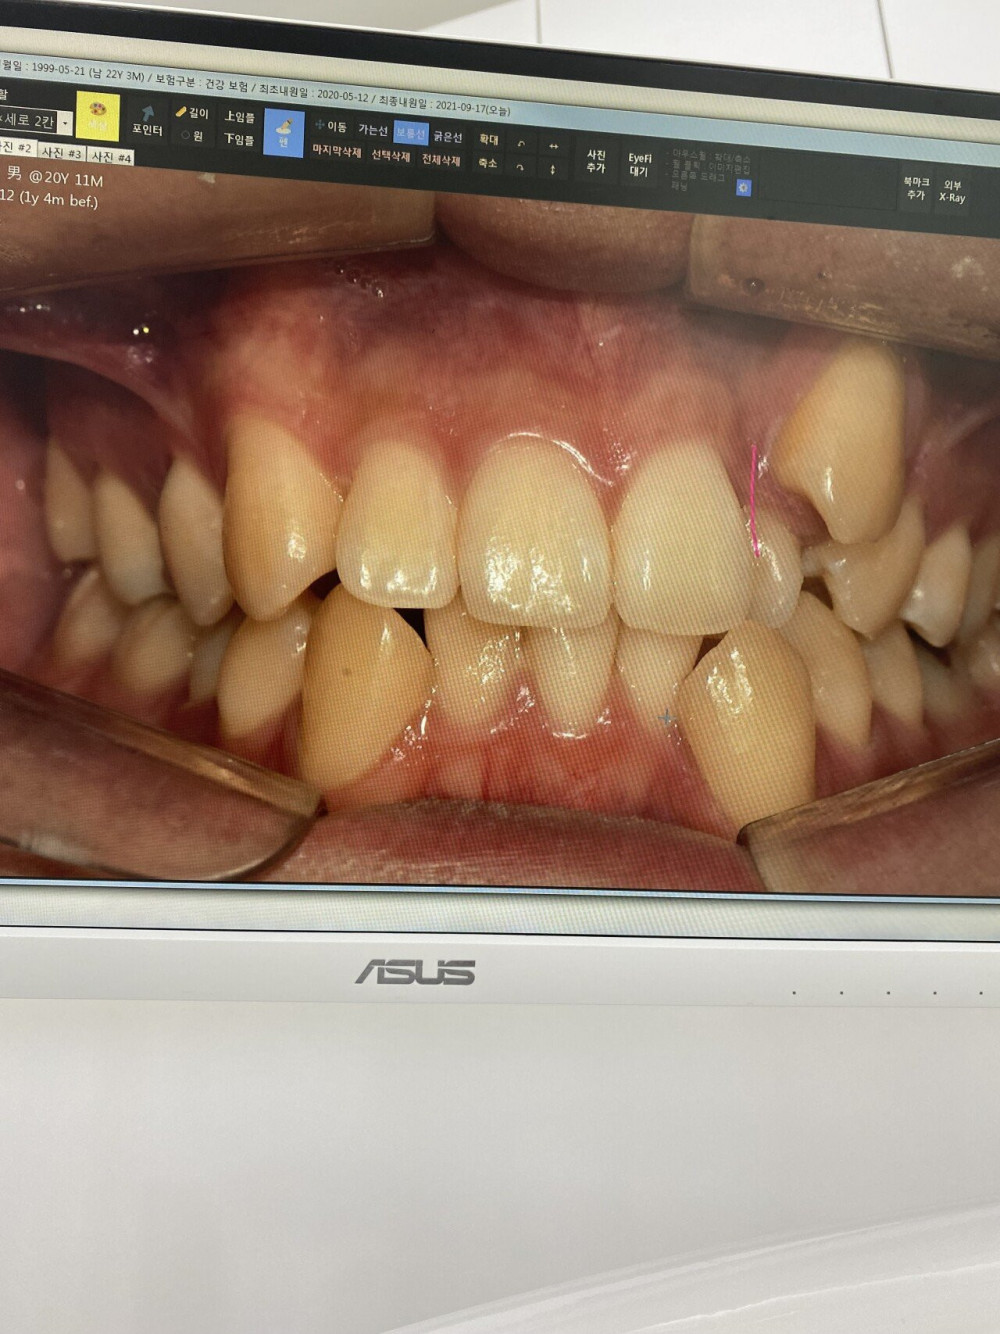

2년 7개월간의 교정이 끝난 펨코인